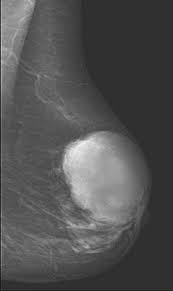

Фиброаденома

Фиброаденома - доброкачественная опухоль молочных желез из компонентов соединительной ткани. Это самый частый вариант доброкачественных опухолей молочных желез.

При осмотре определяется в виде плотного узла, с четкими границами.

Для диагностики у пациенток до 30 лет, как правило, используется УЗИ, в старшем возрасте маммография. При сложных клинических случаях возможно проведение МРТ.